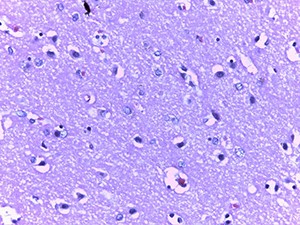

Рисунок 1. Центральный хроматолиз в ядрах эндотелия и перицитов мелкого сосуда с деструкцией стенки (окраска гематоксилином и эозином, ґ200).Микроскопическое исследование при окраске гематоксилином и эозином показало характерные изменения ядерного хроматина в эндотелиальных клетках сосудов микроциркуляторного русла (МЦР) головного мозга и в меньшей степени в периваскулярных астроцитах и ганглиозных клетках (см. рис. 1).

Так, имел место очаговый лизис хроматина с формированием небольшой внутриядерной вакуоли и распылением остатков хроматина ближе к внутреннему листку ядерной мембраны.

В ряде случаев описанная вакуоль содержала гиперхромную базофильную частицу по типу внутриядерного включения. Отмечалась тенденция к увеличению размеров данных вакуолей, которые в последующем занимали большую часть ядра и в конечном итоге приводили к полному нуклеолизу. Контуры клеток в виде остатков цитоплазмы сохранялись какое-то время.

Данные изменения ядерного хроматина имели место в сосудах МЦР всех отделов головного мозга, но более заметными были в коре больших полушарий и сером веществе подкорковых ядер.